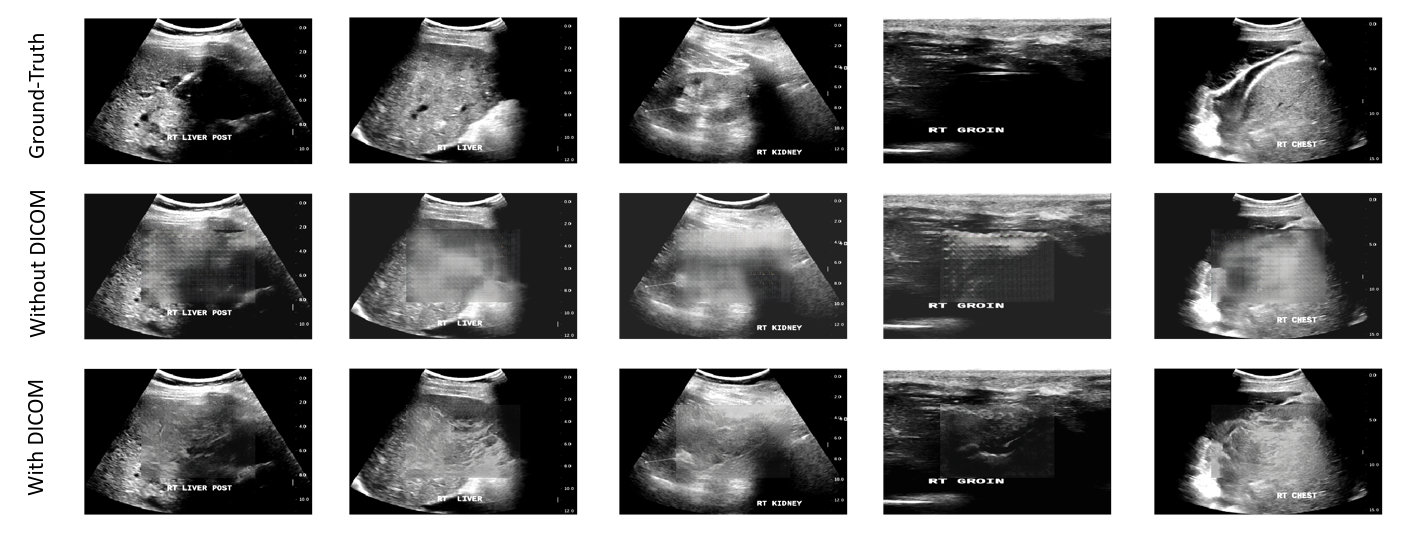

The qualitative results of the context encoder with and without DICOM tags are shown in Figure 3. We observed that trainings without DICOM tags are more prone to modal collapse in our experiments, making it difficult to obtain optimal results. With DICOM tags, the generated images look sharper and can resemble the actual organ texture like liver and kidney(Figure 3). It shows that the joined weakly-supervised training with DICOM tags did improve the image generation quality.

Refer to caption

Figure 3: Example of semantic in-painting results.